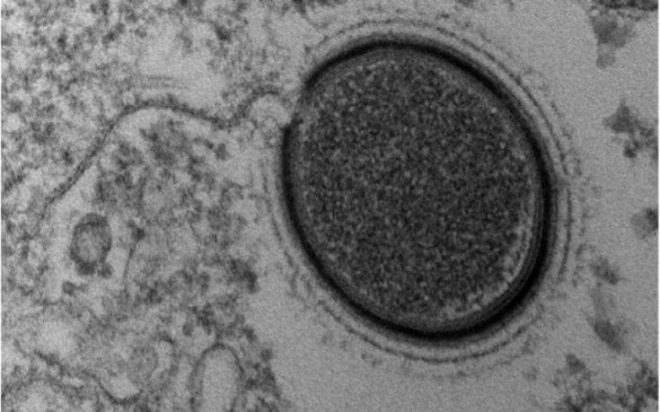

Παγκόσμιο ΣΟΚ: Μεταδοτικό το Αλτσχάϊμερ;

Οι άνθρωποι είναι πιθανό ότι μπορεί να κολλήσουν τη νόσο Αλτσχάιμερ στη διάρκεια κάποιας χειρουργικής επέμβασης ή άλλης ιατρικής διαδικασίας, με τον ίδιο τρόπο που είναι δυνατό να μεταδοθεί... Read more »